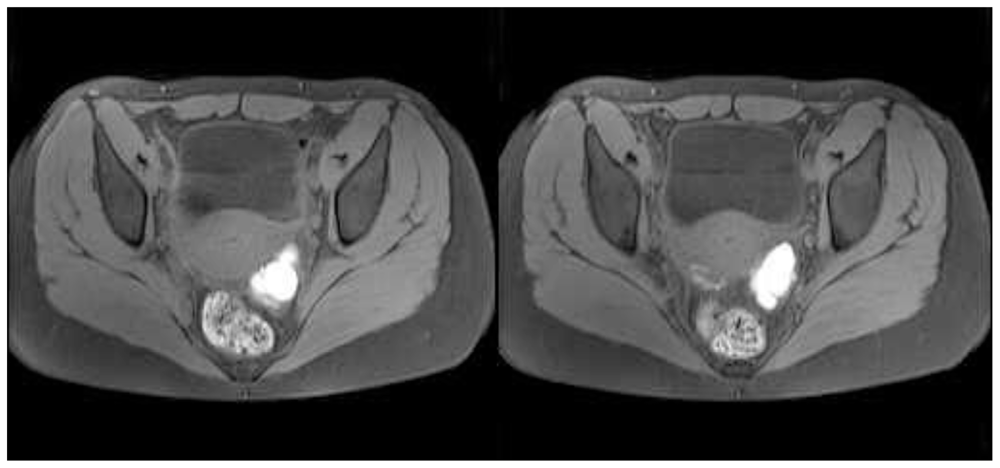

2. Case Presentation and Discussion